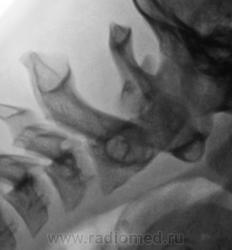

Согласен с мнением Валентина Львовича - сегмент вызывает сомнения. Щель атланто - осевого сустава должна быть шириной около 2 мм и иметь одинаковую ширину на всем протяжении. В данном случае - явное расширение щели в верхних отделах. Так что по крайней мере - нестабильность - прощай Дзю-до...

Кроме этого - структура зуба - это артефакты или...

У Садофьевой:

"Критерием нормы анатомических соотношений в срединном атлантоосевом суставе является высота рентгеновской суставной щели не более 2 мм, одинаковая на всем протяжении. Однако следует учитывать, что данный критерий действителен только при выполнении рентгенограммы в правильной укладке, т. е. при среднем положении головы. На рентгенограммах, произведенных при сгибании или разгибании шеи, рентгеновская суставная щель срединного атланто-осевого сустава может приобретать клиновидную форму и в норме."

Но меня учили, что у детей ширина щели срединного атланто-осевого сустава в норме до 4 мм (у взрослых - 2), что подтверждено личной практикой.

Остается не понятным, и это, изолированное увеличение расстояния между остистыми отростками (дугами) в сегменте С! - С2. Может быть "связочная несостоятельность" (нестабильность).

При этом говорится, что необходим боковой снимок в стандартной боковой проекции (у нас только в сгибании), а также количественные показатели нестабильности: 1. Определение заднего атлантоаксиального промежутка или продольного размера позвоночного канала. Это расстояние между задней поверхностью зубовидного отростка позвонка СII до передней поверхности дуги позвонка СI. В норме оно составляет 17 ± 0,5 мм. Уменьшение величины канала менее 10 мм свидетельствует о переднем подвывихе.

2. Определение переднего атлантоаксиального промежутка. Это расстояние между внутренней поверхностью передней дужки позвонка СI и передней поверхностью зубовидного отростка позвонка СII (сустав Крювелье). В норме у взрослого при сгибании головы вперед этот промежуток не превышает 3 мм, а у ребенка 5 мм. При увеличении этого расстояния можно подозревать передний подвывих.

Измерьте по снимкам, и дело с концом. Но что-то мне говорит, что цифровые значения у данного пациента не выходят за пределы нормы.

Часто встречаю Ваши заключения, очень нравятся....

Я больше насторожен на плавность перехода в позвоночный канал со стороны Блюменбахова ската. Базион должен в норме быть точно над вершиной зуба С2, а линия входа - плавной. В данном наблюдении - явное смещение Базиона кпереди на весь поперечник зуба! И ступеннеообразная деформация линии входа. Тот показатель о котором пишете Вы - продольный размер позвоночного канала - из этой же "оперы". Но измерять его нужно именно тогда, когда это патологическое состояние проявляется - то есть при нагрузке (в данном случае - сгибании!!!) А стоя с прямой шеей - все будет в норме!

Так что считаю, что, независимо от того, что мы увидим на снимке в стандартной боковой проекции, в нашем случае нестабильность есть, и игнорировать ее в плане спорта - никак нельзя, но клиническое ее значение должно быть оценено опытным вертебрологом...